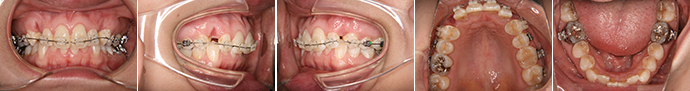

| 主訴 | 上の前歯が出ている、下の前歯がデコボコ |

| 年齢・性別 | 26歳 / 女性 |

| 治療方針 | 顎関節に少し問題があるAngleⅠ級上下顎前突。患者の希望もあり、できるだけ前歯を後退して口元の突出感の改善を行う。 |

| 抜歯部位 | 小臼歯4本抜歯 |

| 使用装置 | ホールディングアーチ、マルチブラケット装置 |

| 治療期間 | 26か月 |

| リテーナー | 上顎インビジブル、下顎スプリングリテーナー |

| 費用 | 825,000円(税別) |